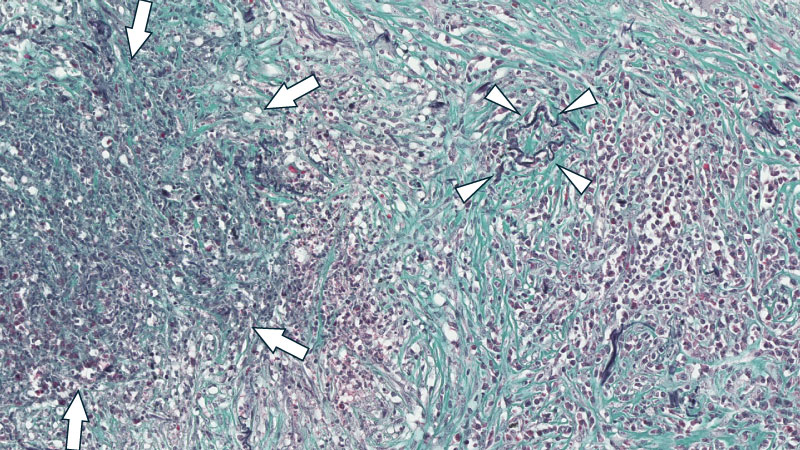

ミクロ像 (Elastica-Masson染色 中拡大): 著明な好中球浸潤を伴う壊死部(矢印)とそれを取り囲む肉芽腫性病変。HE染色で判別が難しかった巻き込まれた血管(矢頭)との区別が、明確になった。